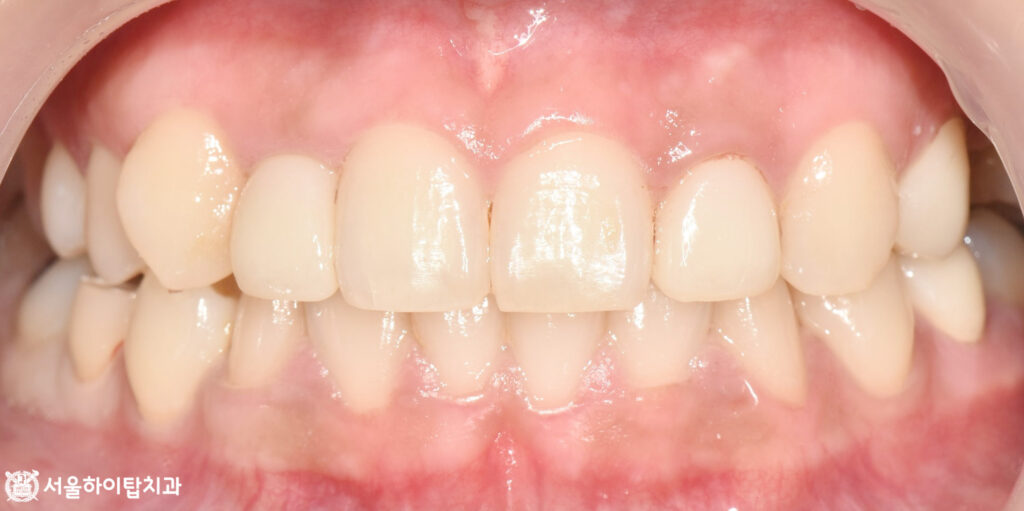

5. 최종 결과

주안역 치과 에서 최종 모습을

예시 자료를 통해 보여드리겠습니다.

최종적으로 크라운이 부착된 모습입니다.

보철은 지르코니아 크라운으로 제작되어,

주변 자연치들과 자연스럽게 어우러지며

앞니의 위치와 형태에 맞게 심미성이

한층 더 향상된 것을 확인할 수 있습니다.